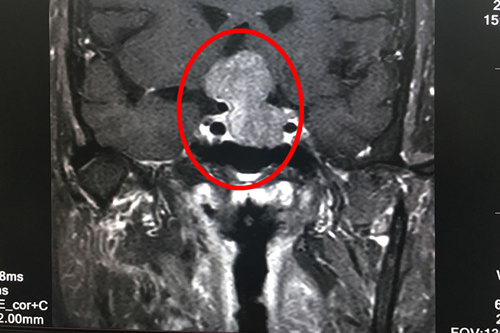

術(shù)前核磁共振顯示:垂體巨大腺瘤(畫圈部分)